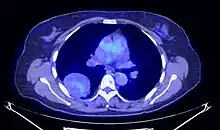

Le TEP scanner est utilisé afin de caractériser l'activité métabolique de la tumeur et de la différencier des tumeurs malignes. Le traceur est fixé de manière hétérogène et peu intense[41],[23].

Coupe axiale de TEP thoracique.

Tumeur fibreuse solitaire pleurale au TEP scanner.